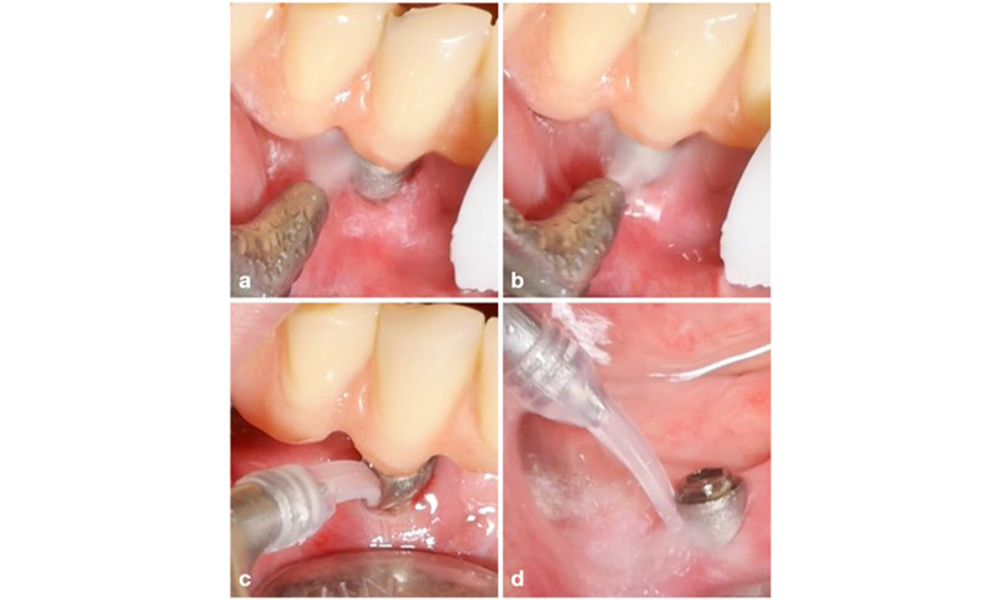

Изборът на средство зависи от клиничните обстоятелства, като например разликата между зъбен камък и мека плака. По този начин, в случаите със зъбен камък първо трябва да се използват титаниеви или пластмасови кюрети или специални накрайници за ултразвукови скалери, последвани от използването на устройство за въздушно полиране (фигура 7). В случаите само с натрупване на мека плака може да е достатъчно само въздушно полиране. Устройствата за въздушно полиране са лесни за ползвателя и пациента и са поне толкова ефективни, колкото стандартните инструменти (Schwarz et al. 2015a).

Случай на пациент с периимплантатен мукозит, лоша орална хигиена и натрупване на зъбен камък (a). В този случай е препоръчително комбинирането на различни устройства. Например за отстраняване на зъбния камък са необходими специални накрайници за ултразвукови скалери (b), докато останалия мек биофилм може да се отстрани с устройство за въздушно полиране (c–d).

Фигура 7. Случай на пациент с периимплантатен мукозит, лоша орална хигиена и натрупване на зъбен камък (a). В този случай е препоръчително комбинирането на различни устройства. Например за отстраняване на зъбния камък са необходими специални накрайници за ултразвукови скалери (b), докато останалия мек биофилм може да се отстрани с устройство за въздушно полиране (c–d).